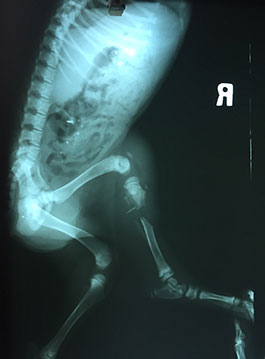

小濱濱是一個無家可歸且右後腳斷掉的幼犬,被一位小姐撿到帶來醫院治療,原本小姐是想去海邊附近尋找被遺棄的小貓,結果卻看見做一半愛心的情侶將小濱濱放置高高的河堤上,當時小姐詢問他們為何要把小濱濱丟棄在那,情侶說明他們是在馬路上看到小濱濱腳斷了,很可憐,帶牠去醫院檢查,但付不出醫藥費,就把牠遺棄放置那裏,緊接著就離開了,留下徬徨無措的小濱濱,小姐不忍心小濱濱獨自待在又高又偏僻的地方受苦,就帶來與協會合作的醫院進行治療。

醫師看了小濱濱的狀況也照了X光,發現小濱濱的骨頭已被細菌吞噬掉了,不過醫師並沒有放棄牠,前前後後進行了三次手術,小濱濱意志堅強,不僅撐過每個療程,並且在復健後能正常行走;復原後的小濱濱,每天都很好動,跑來跑去呢!現在的小濱濱已經找到牠幸福的歸屬囉。